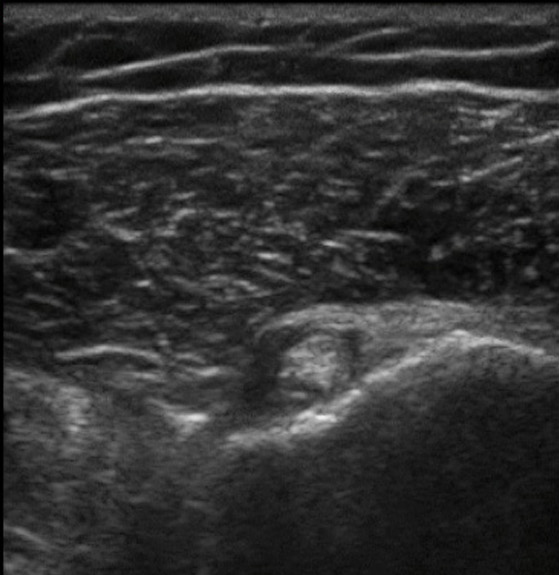

肩部二头肌腱 - 横切切面异常图像